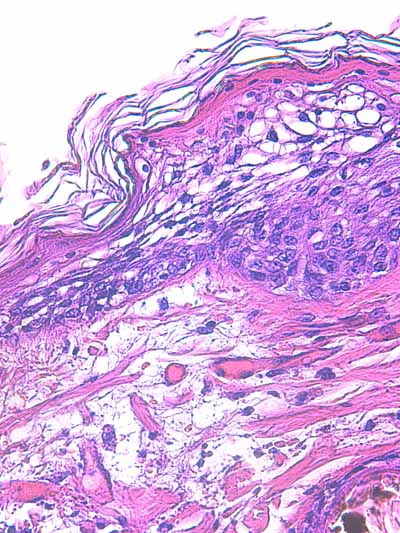

Photo 2 (Hémalun Eosine X 40) : biopsie réalisée en marge d’un ulcère.

L’épiderme, fragilisé, se détache artéfactuellement et se désolidarise du derme superficiel.

Le derme montre une plage cellulaire dense qui s’étend du derme superficiel jusqu’au derme profond.

En contact avec cette plage, se trouve un follicule pileux dont la tige pilaire est fragmentée

et circonvolutée dans son fourreau épithélial.

Légendes de la Photo 2 :

- Pointe de flèche orange : ulcère

- Ovale jaune : plage cellulaire inflammatoire s’étendant du derme superficiel au derme profond

- Flèche turquoise : follicule pileux dont la tige pilaire est fragmentée et circonvolutée dans son fourreau épithélial

- Flèches jaunes : épiderme fragilisé qui se détache du derme

- Double flèche orange : épaisseur épidermique

- Double flèche verte : épaisseur dermique

- Double flèche bleue : épaisseur hypodermique